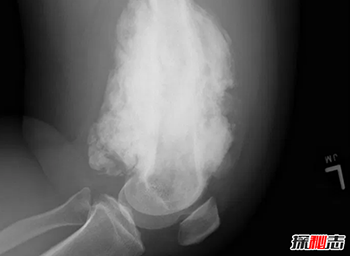

1、黑变病

人骨为什么那么可怕-人体骨骼的十大疯狂事实762 / 作者:网上的人生 / 帖子ID:52913

人类骨骼中最不寻常的疾病之一是恶性软骨病。这是一种在人类身上发现的非常罕见的疾病,只影响到1%的人口。在这种疾病中,一根非常坚硬的骨头以不规则的方式生长在已经存在的骨头上。在X光研究中,这种骨的生长看上去就像蜡烛蜡。

本病的发病原因可能是遗传因素,而环境因素则加重了本病的症状。临床表现为极度疼痛、肢体功能受限、畸形等。